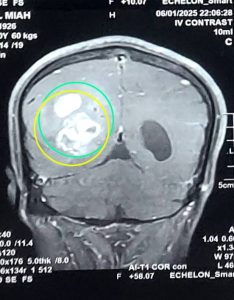

জিবিএম (Glioblastoma Multiforme - GBM)

GBM (Glioblastoma multiforme) হলো মস্তিষ্কের একটি অত্যন্ত আক্রমণাত্মক এবং দ্রুত বর্ধনশীল ক্যান্সার। এটি গ্রেড IV টিউমার হিসেবে শ্রেণীবদ্ধ, যা সবচেয়ে গুরুতর। GBM-এর চিকিৎসায় সার্জারি একটি গুরুত্বপূর্ণ ভূমিকা পালন করে, এরপর সাধারণত রেডিয়েশন থেরাপি এবং কেমোথেরাপি দেওয়া হয়।